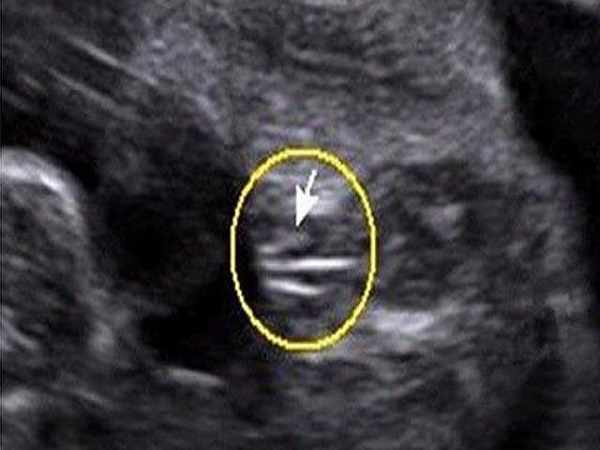

女孩腿部间的B超图片

2、女孩:在怀孕16周的时候,胎儿的生殖器官已经发育比较完全了,B超检查报告单中如果胎儿腿部间出现了三条白线,那就是女孩子***的形状,也就说明女性怀的是个女宝宝。